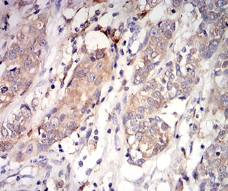

IHC    1/200 - 1/1000